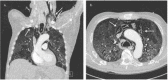

Chest CT showing (A) a right-sided apical pneumothorax and subcutaneous emphysema up to the left side of the neck and (B) extensive pneumomediastinum * Paw: airway pressure (cmH2O), Pes: esophageal pressure (cmH2O), PL: transpulmonary pressure (cmH2O)